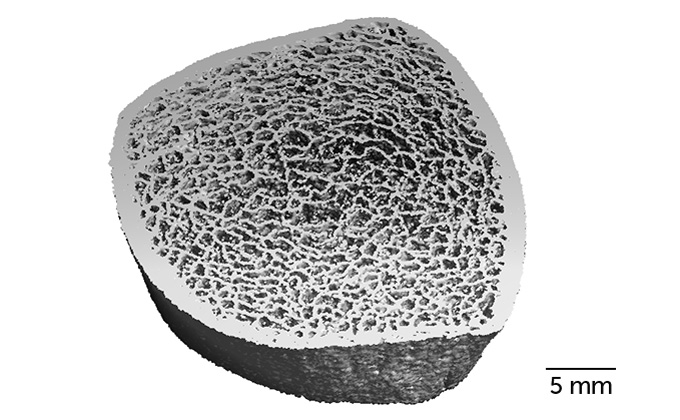

Gabel ve meslektaşları, uzayda dört ila yedi ay geçiren ve yaş ortalamaları 47 olan 17 astronotun kemik yapılarını incelediler. Araştırmacı ekip, alt bacaktaki kaval kemiğinin kemik yapısını görüntülemek için çok detaylı incelemeler gerçekleştirebilen son model tomogrofi cihazları kullandı.

HR-pQCT olarak adlandırılan bu cihazlar, insan saçı kalınlığından daha ince detayları 61 mikronluk ölçeklerde 3 boyutlu mikro mimarisi ile ölçebilen yüksek çözünürlüklü tomografik görüntüler elde edebiliyor. Ayrıca ekip, uzay uçuşundan önce bu tomografik görüntüleri, astronotların uzaydan döndüklerinden altı ay ve bir yıl sonra kaydetti ve astronotların kemik gücünü ve yoğunluğunu hesaplamak için kullandı.